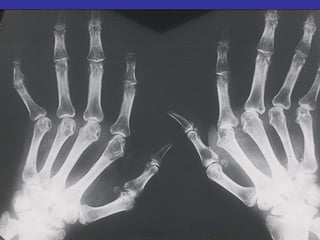

Periarticular Osteopenia

Joint Space Narrowing

Erosions

Mal-Alignment

90% of the joints involved in RA are

affected within the first year

SO TREAT IT EARLY

Disability in Late RA (Too Late)

• Damage

– Bones

– Cartilage

– Ligaments and

other structures

• Fatigue

• Not Reversible

• Have been shown to reduce radiographic

progression (erosions)